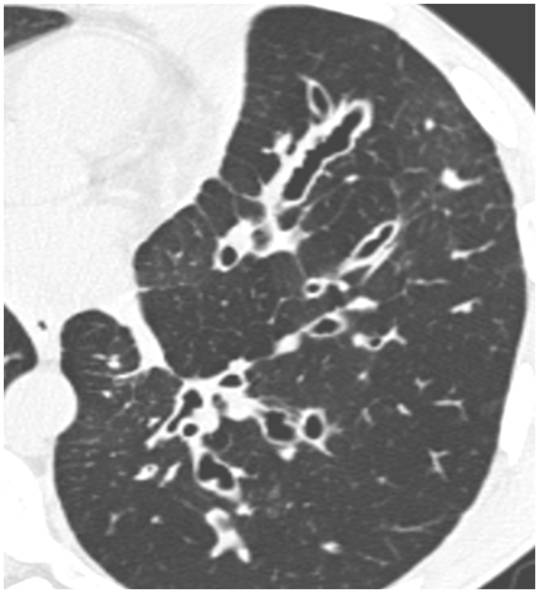

From radiopaedia.org

Image Can Bronchiectasis Be Seen On Xray When asking a radiologist about the definition of bronchiectasis, the answer will. Chest ct scan if indicated (e.g., hemoptysis, or concern for pulmonary. A provider uses a machine to take pictures of your lungs to see if your airways are damaged. Bronchiectasis is dilation and destruction of larger bronchi caused by chronic infection and inflammation. Bronchiectasis and small airways disease.. Can Bronchiectasis Be Seen On Xray.

From radiologykey.com